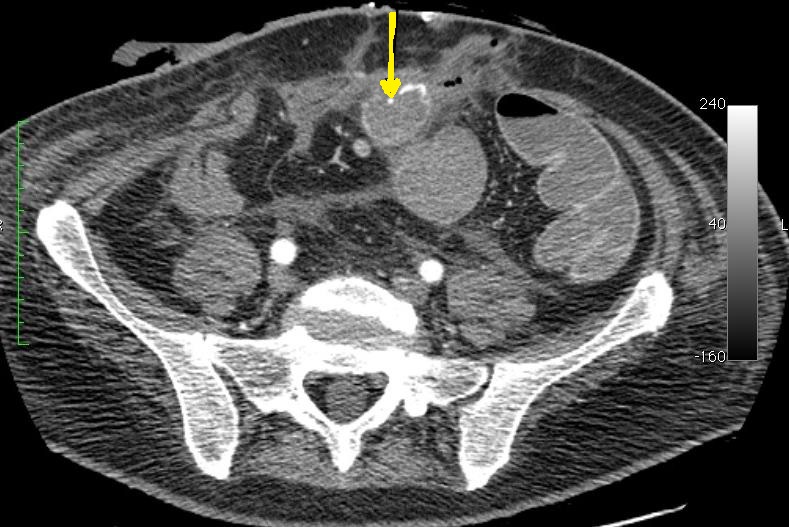

angio + axial MPR of ia enhanced Cone-Beam CT